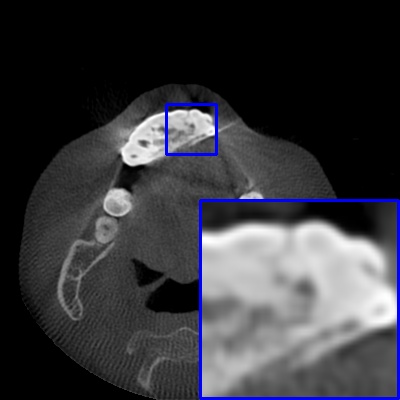

Figure 3: Visual comparison of MAR images by different methods on synthetic MA image. The PSNR (dB)/SSIM results are reported below each image for reference.

Results on synthetic MAR. In Table 1, we provide the quantitative results. One can see that our MARformer-L outperforms the other methods in terms of PSNR and SSIM, but needs only 11.76M parameters and 60.25G FLOPs. Note that the second best method Uformer-B has 50.42M parameters and 205.82G FLOPs. Besides, our MARformer-T achieves similar PSNR and SSIM results with Uformer-T, but needs only 0.40M parameters and 12.82G FLOPs compared to 5.24M and 25.39G for Uformer-T. Our MARformers also achieves faster inference speeds than the Uformers, though with inferior Dice scores, respectively. The qualitative results of visual quality are presented in Fig. 3. We observe that our MARformer-L well recovers the teeth shapes and obtains higher PSNR and SSIM results than the other comparison methods. The light-weight MARformer-L achieves similar results to Uformer-T. All these results validate that our MARformer is more efficient than the comparison methods on dental CBCT MAR.